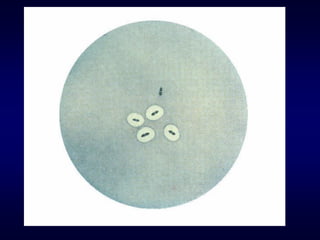

Optochin sensitivity

Pneumococci are sensitive to optochin

(ethylhydrocupreine hydrochloride).

Method: Placing a disc (5 g) on a primary

sputum culture and culturing the plate aerobically

(not in CO2) can help to provide a rapid

Result : The zone of inhibition should be at

least10 mm. Most viridans streptococci and other

alphahaemolytic streptococci are resistant to

optochin. If the zone of inhibition is less than 10

mm (6 mm disc) the colonies should be tested for

bile solubility